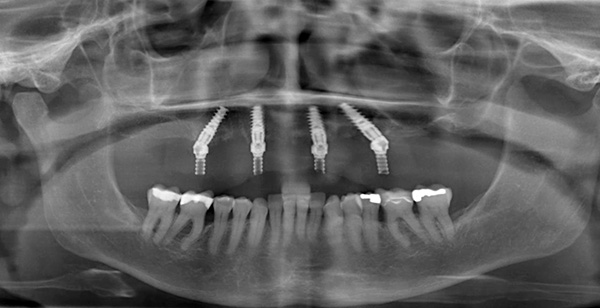

A foto abaixo mostra um exemplo de aparência da dentadura ao usar as duas tecnologias - All-on-4 e All-on-6: